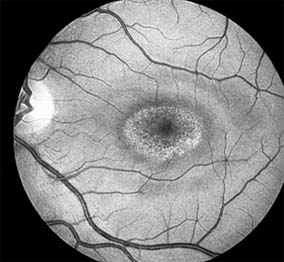

Chapter 10: Retina DISEASES OF THE MACULA AGE-RELATED MACULAR DEGENERATION Age-related macular degeneration is the leading cause of permanent blindness in the elderly. The exact cause is unknown, but the incidence increases with each decade over age 50. Other associations besides age include race (usually Caucasian), sex (slight female predominance), family history, and a history of cigarette smoking. The disease includes a broad spectrum of clinical and pathologic findings that can be classified into two groups: nonexudative ("dry") and exudative ("wet"). Although both types are progressive and usually bilateral, they differ in their manifestations, prognosis, and management. The more severe exudative form accounts for approximately 90% of all cases of legal blindness due to age-related macular degeneration. 1. NONEXUDATIVE MACULAR DEGENERATION Nonexudative age-related macular degeneration is characterized by variable degrees of atrophy and degeneration of the outer retina, retinal pigment epithelium, Bruch's membrane and choriocapillaris. Of the ophthalmoscopically visible changes in the retinal pigment epithelium and Bruch's membrane, drusen are the most typical (Figure 10-1). Drusen are discrete, round, yellow-white deposits of variable size beneath the pigment epithelium and are scattered throughout the macula and posterior pole. With time, they may enlarge, coalesce, calcify, and increase in number. Histopathologically, most drusen consist of focal collections of eosinophilic material lying between the pigment epithelium and Bruch's membrane; they therefore represent focal detachment of the pigment epithelium. In addition to drusen, clumps of pigment irregularly dispersed within depigmented areas of atrophy may progressively appear throughout the macula. The level of associated visual impairment is variable and may be minimal. Fluorescein angiography demonstrates irregular patterns of retinal pigment epithelial hyperplasia and atrophy. Electrophysiologic testing in most patients is normal. There is no generally accepted treatment or means of prevention of this type of macular degeneration. Laser retinal photocoagulation appears to have a beneficial effect on drusen but has not yet been shown to improve visual outcome. Although high plasma levels of antioxidants are associated with a reduced risk of age-related macular degeneration, the use of vitamin supplements does not appear to be preventive. Most patients with macular drusen never experience significant loss of central vision; the atrophic changes may stabilize or progress slowly. However, the exudative stage may develop suddenly at any time, and in addition to regular ophthalmic examinations, patients are given an Amsler grid ( 2. EXUDATIVE MACULAR DEGENERATION Although patients with age-related macular degeneration usually manifest nonexudative changes only, the majority of patients who experience severe vision loss from this disease do so from the development of subretinal neovascularization and related exudative maculopathy. Serous fluid from the underlying choroid can leak through small defects in Bruch's membrane, causing focal detachment of the pigment epithelium. Additional fluid may lead to further separation of the overlying sensory retina, and vision usually decreases if the fovea is involved. Retinal pigment epithelial detachments may spontaneously flatten, with variable visual results, and leave a geographic area of depigmentation at the involved site. Ingrowth of new vessels from the choroid into the subretinal space is the most important change that predisposes patients with drusen to macular detachment and irreversible loss of central vision. These new vessels grow in a flat cartwheel or sea-fan configuration away from their site of entry into the subretinal space. The clinical changes of early subretinal neovascularization are subtle and may be easily overlooked; during this occult stage of new vessel formation, the patient is asymptomatic, and the new vessels may not be apparent either ophthalmoscopically or angiographically. The ophthalmologist must maintain a high index of suspicion that subretinal neovascularization is present whenever a patient with evidence of age-related macular degeneration has sudden or recent central vision loss, including blurred vision, distortion, or a new scotoma. If the fundus examination reveals subretinal blood, exudate, or a grayish-green choroidal lesion in the macula, there is great likelihood that neovascularization is present, and a fluorescein or indocyanine green angiogram should be obtained promptly to determine if a treatable lesion can be identified. Although some subretinal neovascular membranes may spontaneously regress, the natural course of subretinal neovascularization in age-related macular degeneration is toward irreversible loss of central vision over a variable period of time. The sensory retina may be damaged by long-standing edema, detachment, or underlying hemorrhage. Furthermore, a hemorrhagic detachment of the retina may undergo fibrous metaplasia, resulting in an elevated subretinal mass called a disciform scar. This elevated fibrovascular mound of variable size represents the cicatricial end stage of exudative age-related macular degeneration. It is usually centrally located and results in permanent loss of central vision. Treatment In the absence of subretinal neovascularization, no medical or surgical treatment of serous retinal pigment epithelial detachment is of proved benefit. The use of parenteral alpha interferon, for example, has not been effective for this disease. However, if a well-defined extrafoveal ( Krypton laser photocoagulation of juxtafoveal (<200 Following successful photocoagulation of a subretinal neovascular membrane, recurrent neovascularization either contiguous with or remote from the laser scar may occur in one-half of cases by 2 years. Recurrence is often accompanied by severe vision loss, so that careful monitoring with Amsler grids, ophthalmoscopy, and angiography is essential. Low-dose radiotherapy has provided encouraging results in patients with subfoveal neovascularization. Patients with impaired central vision in both eyes may benefit from a variety of low vision aids. CENTRAL SEROUS CHORIORETINOPATHY Central serous chorioretinopathy is characterized by serous detachment of the sensory retina as a consequence of focal leakage of fluid from the choriocapillaris through a defect in the retinal pigment epithelium (Figures 10-2 and 10-3). This disease typically affects young to middle-aged men and may be related to life stress events. Most patients present with the sudden onset of blurred vision, micropsia, metamorphopsia, and central scotoma. Visual acuity is often only moderately decreased and may be improved to near-normal with a small hyperopic correction. The diagnosis is made by slitlamp examination of the fundus; the presence of serous detachment of the sensory retina in the absence of ocular inflammation, subretinal neovascularization, an optic pit, or a choroidal tumor is diagnostic. The retinal pigment epithelial lesion appears as a small, round or oval, yellowish-gray spot that is variable in size and may be difficult to detect without the aid of fluorescein angiography. Fluorescein dye leaking from the choriocapillaris may accumulate below the pigment epithelium or sensory retina, resulting in a variety of patterns including the well-recognized smokestack configuration. Approximately 80% of eyes with central serous chorioretinopathy undergo spontaneous resorption of subretinal fluid and recovery of normal visual acuity within 6 months after the onset of symptoms. Despite normal acuity, however, many patients have a mild permanent visual defect, such as a decrease in color sensitivity, micropsia, or relative scotoma. Twenty to 30 percent of patients will have one or more recurrences of the disease, and complications-including subretinal neovascularization and chronic cystoid macular edema-have been described in patients with frequent and prolonged serous detachments. The cause of central serous chorioretinopathy is unknown; there is no convincing evidence that the disease is either infectious or due to retinal pigment epithelial dystrophy. Argon laser photocoagulation directed to the active leak significantly shortens the duration of the sensory detachment and hastens the recovery of central vision, but there is no evidence that prompt photocoagulation reduces the chance of permanent loss of visual function. Although the complications of retinal laser photocoagulation are few, it is probably not advisable to recommend immediate photocoagulation treatment in all patients with central serous chorioretinopathy. The duration and location of disease, the condition of the fellow eye, and occupational visual requirements are all considerations upon which treatment decisions are based. MACULAR EDEMA Retinal edema involving the macula may be associated with a variety of intraocular inflammatory diseases, retinal vascular diseases, intraocular surgery, inherited or acquired retinal degenerations, medications, macular membranes, or unknown causes. Macular edema may be diffuse, with nonlocalized intraretinal fluid causing thickening of the macula. When edema fluid accumulates in honeycomb-like spaces of the outer plexiform and inner nuclear layers, it is called cystoid macular edema. On fluorescein angiography, fluorescein dye leaks from the perifoveal retinal capillaries and accumulates in a flower-petal pattern about the fovea (Figure 10-4). The most widely recognized association with cystoid macular edema is intraocular surgery. Approximately 50% of eyes undergoing uneventful intracapsular cataract extraction and 20% of eyes undergoing extracapsular cataract extraction develop angiographic cystoid macular edema. Clinically significant edema usually occurs within 4-12 weeks postoperatively, but in some instances its onset may be delayed for months or years. Many patients with cystoid macular edema of less than 6 months' duration have self-limited leakage that will resolve without treatment. Topical or local (or both) anti-inflammatory therapy may be of value in restoring visual acuity in some patients with chronic postoperative macular edema. YAG laser vitreolysis (see Chapter 24) and surgical vitrectomy may be of benefit when the macular edema is associated with vitreous tissue incarcerated in the cataract wound or adherent to anterior segment structures. When an intraocular lens implant is the cause of postoperative macular edema due to its design, positioning, or inadequate fixation, removal of the lens implant can be considered. INFLAMMATORY DISORDERS INVOLVING THE MACULA Presumed Ocular Histoplasmosis Syndrome (Figures 10-5, 10-6 and 10-7) In this disease, serous and hemorrhagic detachments of the macula are associated with multiple peripheral atrophic chorioretinal scars and peripapillary chorioretinal scarring (see Chapter 7). The syndrome usually occurs in healthy patients between the third and sixth decades of life, and the scars are probably caused by an antecedent subclinical systemic infection with Histoplasma capsulatum. The macular detachments are due to subretinal neovascularization, and the visual prognosis depends on the proximity of the neovascular membrane to the center of the fovea. If the membrane extends inside the foveal avascular zone, only 15% of eyes will retain 20/40 vision. A macular scar may change over time, and 10% of patients with normal maculae will develop new atrophic scars in this region. The relative risk of developing macular subretinal neovascularization in the second eye of an affected patient is significant, and these patients should be instructed in the frequent use of the Amsler grid and the importance of prompt examination when changes are detected. Argon laser photocoagulation of a subretinal neovascular membrane outside the foveal avascular zone in symptomatic patients is of value in preventing severe vision loss. The surgical removal of submacular membranes may prove useful in preserving vision. Acute Multifocal Posterior Placoid Pigment Epitheliopathy (AMPPPE) AMPPPE typically affects healthy young patients who develop rapidly progressive bilateral vision loss in association with ophthalmoscopically visible multifocal flat gray-white subretinal lesions involving the pigment epithelium (Figure 10-8). The cause of this disease, which in many instances is associated with evidence of an influenza-like illness, is unknown; the course and nature of the illness suggests the possibility of viral infection. The characteristic feature of the disease is the rapid resolution of the fundus lesions and a delayed return of visual acuity to near-normal levels. Although the prognosis for visual recovery in this acute self-limited disease is good, many patients will identify small residual paracentral scotomas when carefully tested. Extensive pigmentary changes remaining during the late stages of AMPPPE may mimic widespread retinal degeneration; the clinical history and normal electrophysiologic findings aid in this differential diagnosis. Geographic Helicoid Peripapillary Choroidopathy This is a chronic progressive and recurrent multifocal inflammatory disease of the retinal pigment epithelium, choriocapillaris, and choroid. It characteristically involves the juxtapapillary retina and extends radially to involve the macula and peripheral retina. The active stage manifests itself as sharply demarcated gray-yellow lesions with irregular borders that appear to involve the pigment epithelium and choriocapillaris. Vitritis, anterior uveitis, and subretinal neovascularization have been associated with this disorder. Involvement is usually bilateral, and the cause is unknown. The natural history of this indolent inflammatory disease is variable and may correlate with the presence of disease in the fellow eye. Local or systemic corticosteroid treatment may be of benefit when active inflammation is present; laser photocoagulation is administered as indicated for the complication of subretinal neovascularization. Vitiliginous Chorioretinitis (Birdshot Retinochoroidopathy) This is a syndrome characterized by diffuse cream-colored patches at the level of the pigment epithelium and choroid, retinal vasculitis associated with cystoid macular edema, and vitritis. The associations with HLA-A29 and with retinal S-antigen suggest that this disease has a genetic predisposition and that retinal autoimmunity plays a role in its manifestations. In many cases, electroretinography, electro-oculography, and dark adaptation studies are abnormal. The course of the disease is that of exacerbation and remission with variable visual outcomes; visual loss has been attributed to chronic cystoid macular edema, optic atrophy, macular scarring, or subretinal neovascularization. Corticosteroid therapy has not proved effective against this disease. Acute Macular Neuroretinopathy Acute macular neuroretinopathy is characterized by the acute onset of paracentral scotomas and mild visual acuity loss accompanied by wedge-shaped parafoveal retinal lesions in the deep sensory retina of one or both eyes. The macular lesions are subtle, reddish-brown, and best seen with a red-free light. The patients are usually young adults with a history of acute viral illness. While the retinal lesions may fade, the scotomas tend to persist and remain symptomatic. Multiple Evanescent White Dot Syndrome This is an acute and self-limited unilateral disease that affects mainly young women and is characterized clinically by multiple white dots at the level of the pigment epithelium, vitreal cells, and transient electroretinographic abnormalities. The cause is unknown. There is no evidence of associated systemic disease. The retinal lesions gradually regress in a matter of weeks, leaving only minor retinal pigment epithelial defects. ANGIOID STREAKS Angioid streaks appear as irregular, jagged tapering lines that radiate from the peripapillary retina into the macula and peripheral fundus (Figure 10-9). The streaks represent linear crack-like dehiscences in Bruch's membrane. The lesions are rarely noted in children and probably develop in the second or third decade of life. Early in the disease the streaks are sharply outlined and red-orange or brown. Subsequent fibrovascular tissue growth may partially or totally obscure the streak margins. Nearly 50% of patients with angioid streaks have an associated systemic disease. Pseudoxanthoma elasticum, Paget's disease of bone, Ehlers-Danlos syndrome, and several hemoglobinopathies and hemolytic disorders have been associated with this retinal disease, but the most common association is with age-related degeneration of Bruch's membrane. Patients with angioid streaks should be warned of the potential risk of choroidal rupture from even relatively mild eye trauma. Older patients with the disease are at risk of developing serous and hemorrhagic detachments of the retina as a consequence of subretinal neovascularization. Laser treatment may be used to photocoagulate extrafoveal neovascular membranes; however, other neovascular membranes are likely to occur. Prophylactic treatment of angioid streaks before subretinal neovascularization develops is not recommended. MYOPIC MACULAR DEGENERATION Pathologic myopia is one of the leading causes of blindness in the United States and is characterized by progressive elongation of the eye with subsequent thinning and atrophy of the choroid and pigment epithelium in the macula. Peripapillary chorioretinal atrophy and linear breaks in Bruch's membrane ("lacquer cracks") are characteristic findings on ophthalmoscopy (Figure 10-10). The degenerative changes of the macular pigment epithelium resemble those found in the older patient with age-related macular degeneration. A characteristic lesion of this disease is a raised, circular, pigmented macular lesion called a Fuchs spot. Most patients are in the fifth decade when the degenerative macular changes cause a slowly progressive loss of vision; rapid loss of visual acuity is usually caused by serous and hemorrhagic macular degeneration overlying a subretinal neovascular membrane. Fluorescein angiography in patients with pathologic myopia may show delayed filling of choroidal and retinal blood vessels. Angiography is helpful in identifying and locating the site of subretinal neovascularization in patients who develop serous or hemorrhagic detachments of the macula. Because of the frequent close proximity of the subretinal neovascular membrane to the foveola in these patients, laser photocoagulation may not be possible. As subretinal neovascular membranes tend to remain small and because photocoagulation-associated chorioretinal atrophy tends to progress in patients with pathologic myopia, retinal laser treatment is not as beneficial as in other diseases associated with macular subretinal neovascularization. The chorioretinal changes of pathologic myopia predispose the retina to breaks and thus to retinal detachment. Peripheral retinal findings may include paving stone degeneration, pigmentary degeneration, and lattice degeneration. Retinal breaks usually occur in areas involved with chorioretinal lesions, but they also arise in areas of apparently normal retina. Some of these breaks, particularly those of the "horseshoe" and round retinal tear type, will progress to rhegmatogenous retinal detachment. MACULAR HOLE A macular hole is a partial or full-thickness absence of the sensory retina in the macula. This disorder occurs most often in elderly women and is associated with elevated plasma fibrinogen levels. The typical finding on biomicroscopy of the symptomatic eye is a full-thickness, round or oval, sharply defined hole measuring one-third disk diameter in the center of the macula, which may be surrounded by a ring detachment of the sensory retina (Figure 10-11). With a full-thickness macular hole, visual acuity is impaired and metamorphopsia, as well as a central scotoma, are present on the Amsler grid. An operculum of retinal tissue may overlie the macular hole. Tangential traction from epiretinal vitreous cortex plays an important role in the pathogenesis of macular hole. Early stages of macular hole formation, such as a deep foveal yellow spot or ring, may be reversible as the posterior vitreous cortex spontaneously separates from the retina. Therapy for macular hole disease involves reattaching and potentially restoring function to the retina overlying the cuff of subretinal fluid surrounding the hole. While the anatomic results of vitrectomy surgery to close macular holes are encouraging, the clinical benefits are still under study. EPIRETINAL MACULAR MEMBRANES Fibrocellular membranes may proliferate on the surface of the retina, either in the macula or peripheral retina. Contraction or shrinkage of these epiretinal membranes may cause varying degrees of visual distortion, intraretinal edema, and degeneration of the underlying retina. Biomicroscopy usually shows retinal wrinkles and vessel tortuosity and may rarely also show retinal hemorrhages, cotton-wool spots, serous retinal detachment, and macular hole; a posterior vitreous detachment is nearly always present (Figure 10-12). Disorders associated with epiretinal membranes include retinal tears with or without rhegmatogenous retinal detachment, vitreous inflammatory diseases, trauma, and a variety of retinal vascular diseases. Patients with macular distortion and vision loss caused by epiretinal membrane contraction are usually left with stable visual acuity, suggesting that membrane contraction is a short-lived and self-limited process. Surgical peeling of severe epiretinal membranes can be performed successfully, but regrowth of epiretinal tissues occurs in some cases. There is no role for photocoagulation in the treatment of epiretinal macular membrane disease. TRAUMATIC MACULOPATHY Blunt trauma to the anterior segment of the eye may cause a contrecoup injury to the retina called commotio retinae. The retina develops a gray-white color that affects primarily the outer retina and may be confined to the macular area (Berlin's edema) or may involve extensive areas of the peripheral retina. The retinal whitening in the macular area may clear completely, or impairment of central vision may be permanent and associated with a pigmented retinal scar (Figure 10-13) or a macular hole. Trauma similar to that which causes Berlin's edema may also cause choroidal rupture with subretinal hemorrhage and permanent central vision loss. In addition to blunt trauma, several other traumatic injuries involving the macula are of importance. Purtscher's retinopathy is characterized by multiple patches of superficial retinal whitening and retinal hemorrhages in each eye of a patient after severe compression injury to the head or trunk. Terson's syndrome is seen in approximately 20% of patients after traumatic (or spontaneous) subarachnoid or subdural hemorrhage and is characterized by vitreous and superficial macular hemorrhage. Solar retinopathy refers to a specific foveolar lesion that occurs after sun-gazing and is best described as a usually bilateral sharply circumscribed and often irregularly shaped partial-thickness hole or depression in the center of the fovea. MACULAR DYSTROPHIES Macular dystrophies differ from degenerations in that the former are inherited, though not necessarily evident at birth, and are not associated with systemic diseases. Most often the disorder is restricted to the macula; it may be symmetric or asymmetric, but eventually both eyes are affected. In the early stages of some of these disorders the visual acuity may be reduced while the macular changes are subtle or absent on ophthalmoscopy, and the patient's complaint may be dismissed as spurious. Conversely, in other macular dystrophies, the ophthalmoscopic changes may be very striking at a time when the patient is free of visual symptoms. One method of classifying the more common macular dystrophies is to consider the presumptive anatomic layer or layers of the retina involved (Table 10-1). X-Linked Juvenile Retinoschisis This is a congenital disease of males characterized by a macular lesion called "foveal schisis." On slitlamp examination, foveal schisis appears as small superficial retinal cysts arranged in a stellate pattern accompanied by radial striae centered in the foveal area (Figure 10-14). Visual acuity is usually between 20/40 and 20/200; peripheral visual field abnormalities are present in the 50% of patients with associated peripheral retinoschisis. The posterior pole appears normal on fluorescein angiography, and this may be helpful in the clinical differentiation from cystoid macular edema. B wave abnormalities on the electroretinogram are consistent with the histopathologic finding of intraretinal splitting in the nerve fiber layer. Cone-Rod Dystrophies The cone-rod dystrophies constitute a relatively rare group of disorders that may be regarded as a single entity showing variable expressivity. Most cases are sporadic, but familial cases are usually transmitted by an autosomal dominant inheritance pattern. Cone-rod dystrophy is characterized by predominant involvement of the cone photoreceptors with progressive color vision defects and associated loss of visual acuity. A bilateral and symmetric bulls-eye pattern of depigmentation and a corresponding zone of hyperfluorescence surrounding a central nonfluorescent spot (similar to that seen in chloroquine retinopathy) are the most commonly described biomicroscopic and angiographic changes in these patients (Figure 10-15). As the disease progresses, the electroretinogram shows marked loss of cone function associated with a slight to moderate loss of rod function. Histopathologic study shows absence of macular and paramacular photoreceptors, and there is associated pigment epithelium degeneration. Fundus Albipunctatus Fundus albipunctatus is an autosomal recessive nonprogressive dystrophy characterized by a myriad of discrete small white dots at the level of the pigment epithelium sprinkled about the posterior pole and midperiphery of the retina. Patients are night-blind with normal visual acuity, normal visual fields, and normal color vision. While the electroretinogram and electro-oculogram are usually normal, dark adaptation thresholds are markedly elevated. Retinitis punctata albescens is the less common progressive variant of this dystrophy. Fundus Flavimaculatus (Stargardt's Disease) This is a bilateral and symmetric autosomal recessive disorder characterized by multiple yellow-white fleck lesions of variable size and shape confined to the retinal pigment epithelium (Figure 10-16). Many patients suffer central visual loss in childhood; however, macular involvement and the ultimate visual outcome are variable. Fluorescein angiography is important in differentiating flecks from drusen; the former are usually hypofluorescent. The electroretinogram and electro-oculogram are usually normal. Histopathologic abnormalities are confined to the pigment epithelium; the yellow flecks seen clinically are dense accumulations of lipofuscin within engorged pigment epithelial cells. Vitelliform Dystrophy (Best's Disease) Vitelliform dystrophy is an autosomal dominant disorder with variable penetrance and expressivity with onset usually in childhood. The ophthalmoscopic appearance is variable and ranges from a mild pigmentary disturbance within the fovea to the typical vitelliform or "egg yoke" lesion located within the central macula (Figure 10-17). This characteristic cyst-like lesion is generally quite round and well demarcated and contains homogeneous opaque yellow material lying at the apparent level of the retinal pigment epithelium. The "egg yoke" may degenerate and be associated with subretinal neovascularization, subretinal hemorrhage, and extensive macular scarring. Visual acuity often remains good, and the electroretinogram is normal; the distinctly abnormal electro-oculogram is the hallmark of this disease. PREVIOUS | NEXT Page: 1 | 2 | 3 | 4 | 5 | 6 | 7 | 8 | 9 10.1036/1535-8860.ch10 |